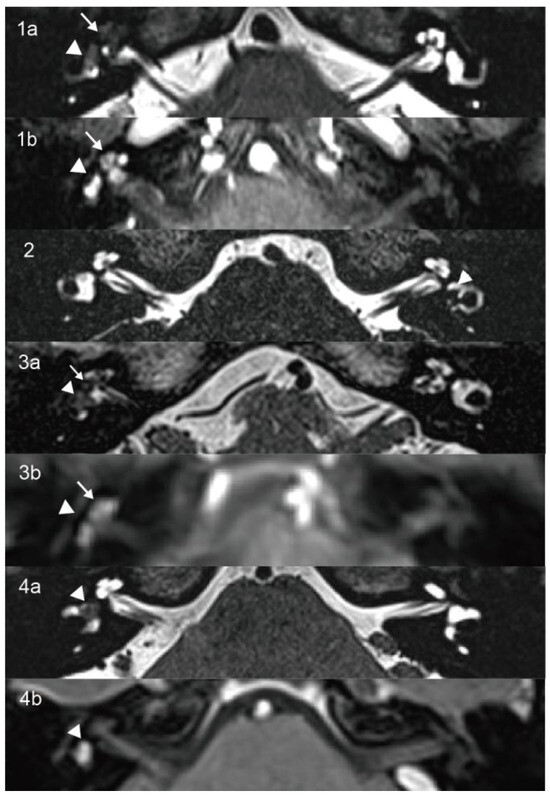

3.1.3. Case 3

| 3 | 65 | F | Recurrent vertigo, tinnitus, HL | Right 8 mm | Intravestibulocochlear | >95 | PSNHL | Normal (0.74/0.88/0.78) | CP = 42% right side hypofunction | Normal | Absent |